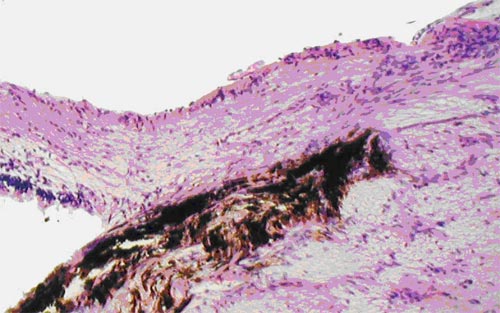

Общее количество ганглиозных клеток было статистически достоверно снижено (р<0,001) по сравнению с группой интактных кроликов и составило 279,00±5,18. Из них мелкие составили 93,50±2,74; средние - 123,83±1,82; крупные - 61,67±3,91. Обнаружено, что при развитии глаукомы снижение количества ганглиозных клеток сетчатки происходило за счет мелких и средних: процент соотношения мелкие/ средние/крупные составил 33/44/22. Резкая атрофия клеток в ганглиозном слое, от каждой из которых отходил аксон, заметно отразилась на толщине их слоя. Толщина слоя аксонов статистически достоверно (р<0,001) была снижена по сравнению с нормой и составляла 78,85±1,86 мкм (рис. 4).

Экспериментальная глаукома. Выраженная атрофия слоя аксонов ганглиозных клеток сетчатки кроликов у диска зрительного нерва. Окраска гематоксилином и эозином. Ув.  200

Рис. 4. Экспериментальная глаукома. Выраженная атрофия слоя аксонов ганглиозных клеток сетчатки кроликов у диска зрительного нерва. Окраска гематоксилином и эозином. Ув. 200

Хотелось отметить, что при атрофии клеток ганглиозного слоя и их аксонов не страдал слой биполярных клеток и фоторецепторов, в котором изменений не было обнаружено.